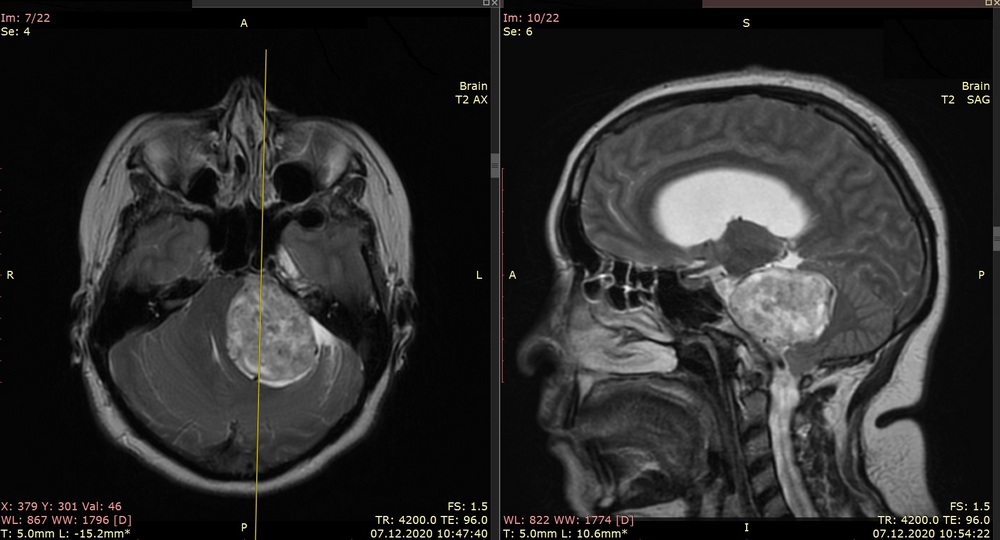

Во время беременности, на сроке 30 недель, женщине резко стало плохо — появились слабость конечностей, затруднение речи и неясность сознания. Врачи по месту жительства выполнили магнитно-резонансную томографию, на которой обнаружили опухоль головного мозга: вестибулярную шванному гигантских размеров.

Поскольку размер образования был очень большим (более 5 см) медики Оренбурга обратились за помощью к коллегам из Петербурга. В ходе телемедицинской консультации врачи приняли решение о необходимости транспортировки пациентки в Центр Алмазова для выполнения хирургического вмешательства. Но до этого оренбургским коллегам предстояло срочно родоразрешить беременную посредством кесарева сечения и выполнить операцию по установке вентрикуло-перитонеального шунта для временного облегчения состояния. Целью этих операций было компенсировать состояние женщины настолько, чтобы она смогла перенести дорогу в Петербург и дождаться операции по удалению опухоли.

«Женщина к нам поступила в тяжелом состоянии, ходить самостоятельно она не могла, плохо говорила. Сложность состояла в том, что шваннома достигла уже очень больших размеров сильно сдавливая жизненно важные отделы головного мозга. Это значительно затрудняло работу нам, хирургам, ведь задача состояла не только в том, чтобы полностью ее удалить, но и не повредить при этом прилежащие к опухоли структуры мозга. Обычно, больше всего в таких ситуациях страдает ствол головного мозга и черепные нервы», — рассказывает научный руководитель нейрохирургического отделения № 6 Центра Алмазова д.м.н. Малик Маратович Тастанбеков.